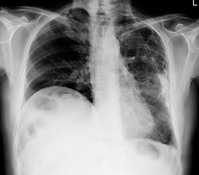

• ±¹³» °áÇ٠ȯÀÚ °¨¼Ò¼¼Áö¸¸, ³ëÀθ¸ Áõ°¡¡¦ 80%´Â ±âħ Áõ»ó ¾ø¾î..

±¹³» °áÇ٠ȯÀÚ °¨¼Ò¼¼Áö¸¸, ³ëÀθ¸ Áõ°¡¡¦ 80%´Â ±âħ Áõ»ó ¾ø¾î..

Çѱ¹Àº 1996³âºÎÅÍ OECD ±¹°¡ Áß °áÇÙ À¯º´·ü 1À§¶ó´Â ¿À¸íÀ» ¾²°í ÀÖ´Ù. ÀÌ·± ¿À¸í¿¡¼­ »¡¸® ¹þ¾î³ª±â À§Çؼ­´Â ³ëÀÎ µî °áÇÙ Ãë¾à °èÃþÀ» ´ë»óÀ¸·Î ÇÑ °ü¸®°¡ ½Ã±ÞÇÏ´Ù. Á¤ºÎ´Â ¿ÃÇØºÎÅÍ µ¶°Å ³ëÀÎ µî °áÇÙ¿¡ Ãë¾àÇÑ ³ëÀÎ ±×·ìÀ» ´ë»óÀ¸·Î ¿¬1ȸ °áÇÙ°ËÁøÀ» ½ÃÇàÇÒ °è..